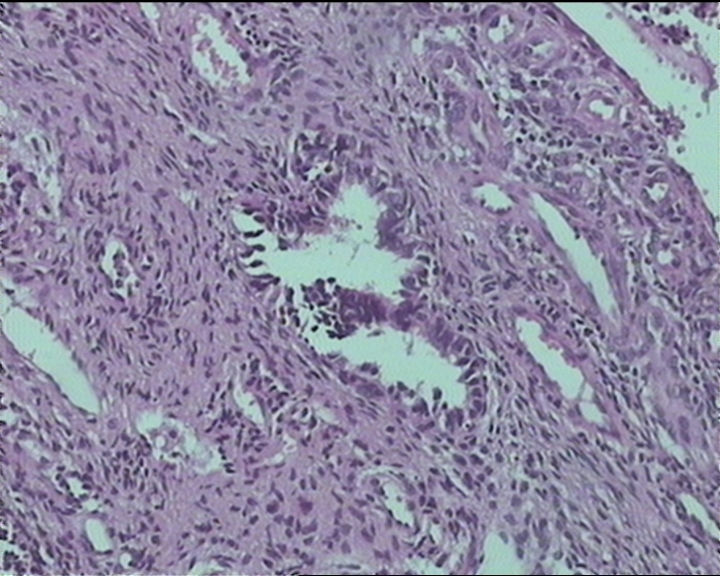

54岁女性,临床“宫颈息肉”送检;巨检:组织一块1。5*1CM,灰红。

细胞及腺体均有异形,图6、11、16象有纤维间质反应,考虑高级别上皮内瘤变/原位癌,腺癌不能除外。

输卵管粘膜化生

It is benign. Benign endocervical polyp with tubal metaplasia.

Sternberg病理学上诊断宫颈原位腺癌的标准是腺体的上皮去粘液分化,呈乳头状或筛网状增生,核分裂易见,这例显然达不到此标准。此例还是归入到腺上皮不典型增生为好。